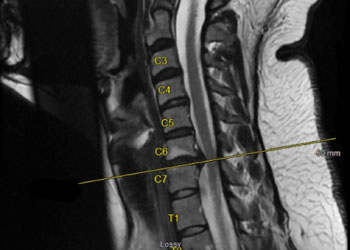

Spine:

Cervical Laminectomy and Fusion

Author: William Sonstein M.D., F.A.C.S., Read More!